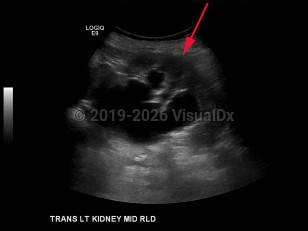

Hydronephrosis